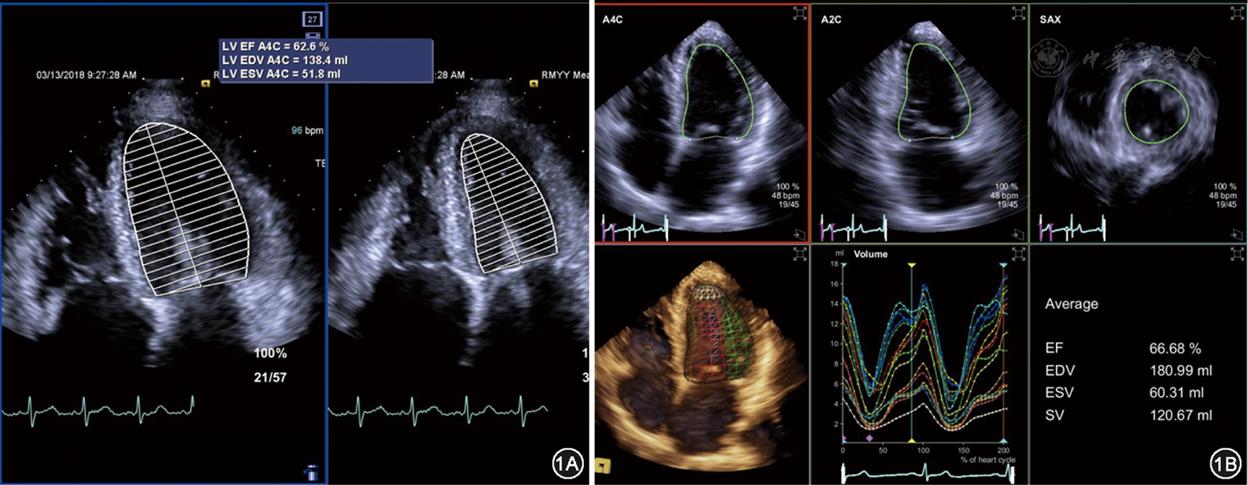

点击查看大图 图1 二维simpson法(图1a)与三维超声心动图测量的左